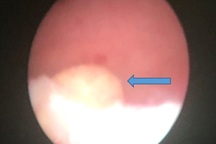

Sỏi thận hay còn gọi là sạn thận là bệnh xảy ra khi các chất khoáng trong nước tiểu lắng đọng lại ở thận, bàng quang, niệu quản... thành những tinh thể rắn. Đây là một bệnh khá phổ biến ở Việt Nam, gặp ở mọi lứa tuổi, trong đó người lớn tuổi chiếm tỷ lệ cao hơn cả. Theo thống kê, cứ khoảng 20 người thì có một người bị sỏi tạo thành trong hệ tiết niệu.

Theo Ths.Bs Nguyễn Đình Liên, Trưởng khoa Ngoại Thận - Tiết niệu, Bệnh viện E Hà Nội, về lý thuyết uống nhiều nước trà, trà đá có nguy cơ gây sỏi thận. Lý do vì trong trà khô chứa nhiều oxalat, một trong những hóa chất quan trọng dẫn đến sự hình thành sỏi thận. Nếu uống trà đặc kèm đá sẽ gây kết tủa thành nước cứng. Oxalate gắn với canxi ion tạo thành tinh thể sỏi trong điều kiện người đó uống ít nước, ra nhiều mồ hôi vì lao động nặng, không khí nóng bức... Những người có tiền sử bị sỏi, uống ít nước, lao động nặng nhọc nếu uống nhiều nước chè sẽ làm gia tăng những cơn đau do sỏi thận.